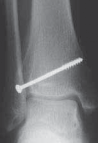

TILLAUX FRACTURES: SALTER-HARRIS TYPE III FRACTURES

1. An anterolateral approach to the ankle is used.

2. This fracture can be fixed by a distal-to-proximal, and anterior-to-posterior, compressive interfragmentary cancellous screw (

TECH FIG 3

).

3. Again, cannulated screw fixation may be used if the surgeon prefers it to the use of noncannulated screws.

22. Crossing the physis is not contraindicated in this fracture pattern because by definition the medial physis is closed and complete physeal closure is imminent.

A B C D

TECH FIG 3•

Tillaux fracture treatment.

A,B.

Tillaux fractures are often not seen clearly on plain radiographic views, and it is important to obtain a mortise view to see the fracture fragment that is obstructed by the fibula in standard AP views.

C,D.

CT scans often aid in fracture characterization and operative planning.

E,F.

These fractures are fixed with compressive interfragmentary cancellous screws across the fracture site, without concern for transphyseal fixation as these patients are always

E F close to skeletal maturity.